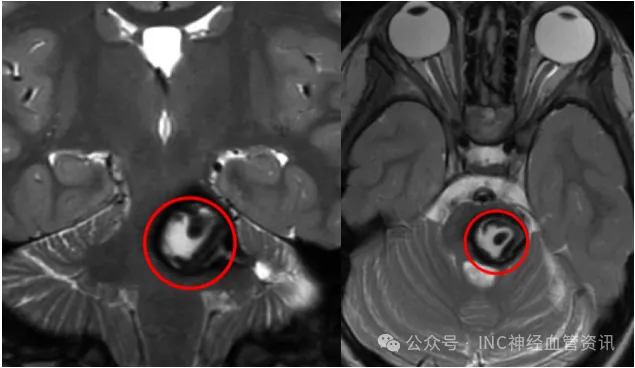

3歲娃突發(fā)偏癱嗜睡,小小頭顱內竟暗藏巨大橋腦海綿狀血管瘤危機!

一個月前,還和其他孩子一樣奔跑嬉戲的阿莉莎毫無征兆地出現(xiàn)劇烈頭痛、嘔吐,病情迅速發(fā)展到右側身體逐漸失靈,面部歪斜。 輾轉就醫(yī)后,MRI結果顯示:腦橋巨大海綿狀血管瘤出血,伴多...

4歲女童西西突發(fā)頭痛嘔吐,被確診為腦干海綿狀血管瘤,面臨手術與觀察的艱難抉擇

媽媽,我這里痛痛的4歲的西西抱著頭向媽媽訴說。起初父母以為孩子只是感冒,但西西的頭痛愈發(fā)頻繁,并伴有惡心嘔吐,精神也越來越差。父母急忙帶她就醫(yī),檢查結果提示中腦占位,混雜...